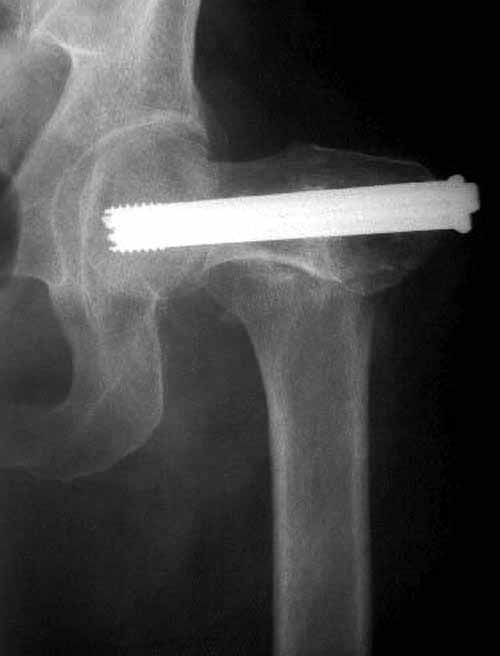

Здесь подобный случай, где стрессовый перелом обнаружен через 2 недели после фиксации. Применен Blade Plate с дополнительными шурупами.